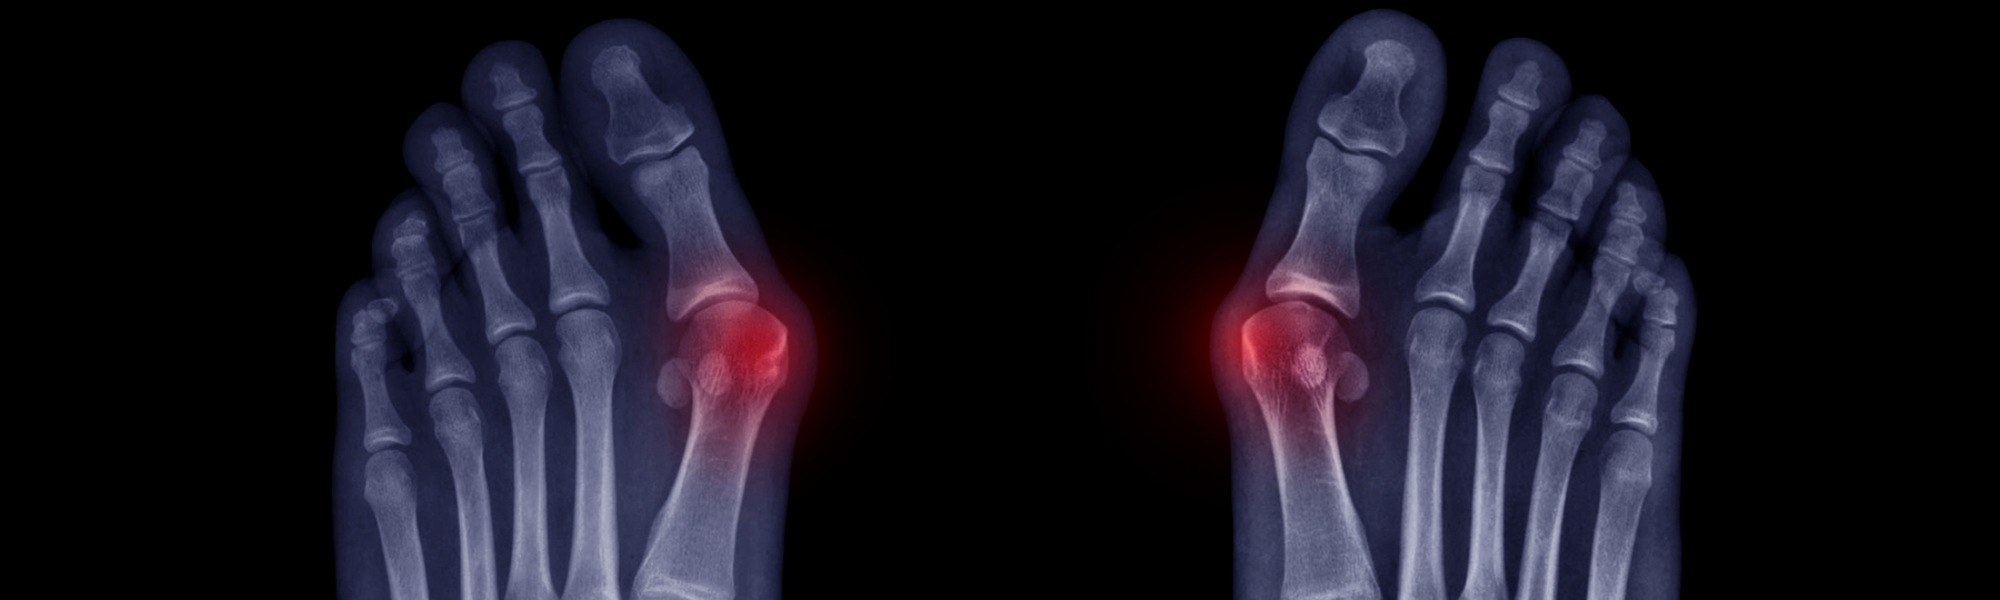

A bunion is more than just an overgrowth of the bone. It's a complex, three-dimensional deformity caused by an unstable joint in the middle of the foot. This instability allows the long bones located in the mid-foot to lean out of alignment, resulting in a bump on the base of the big toe that can be painful and make it difficult to wear certain types of shoes. They can be classified as mild, moderate or extreme and are progressive, meaning they do not resolve on their own without the help of surgery.

Statistics show that almost 25% of U.S. adults suffer from bunions. 87% of these cases involve the metatarsal bone having an irregular rotation. Unfortunately, most traditional bunion surgeries are two-dimensional, focusing only on the visible bump and failing to address the root cause—an unstable joint. When the problem isn't treated correctly, there is a 12x chance the bunion will return.

Lapiplasty 3D Bunion Correction is a groundbreaking procedure designed to treat bunions effectively by addressing all three dimensions of the deformity. Unlike traditional 2D surgeries that merely shave off the bump and shift the top of the bone, Lapiplasty returns the entire bone to its normal alignment, securing the unstable joint. This method offers a higher success rate and a more permanent solution for patients.